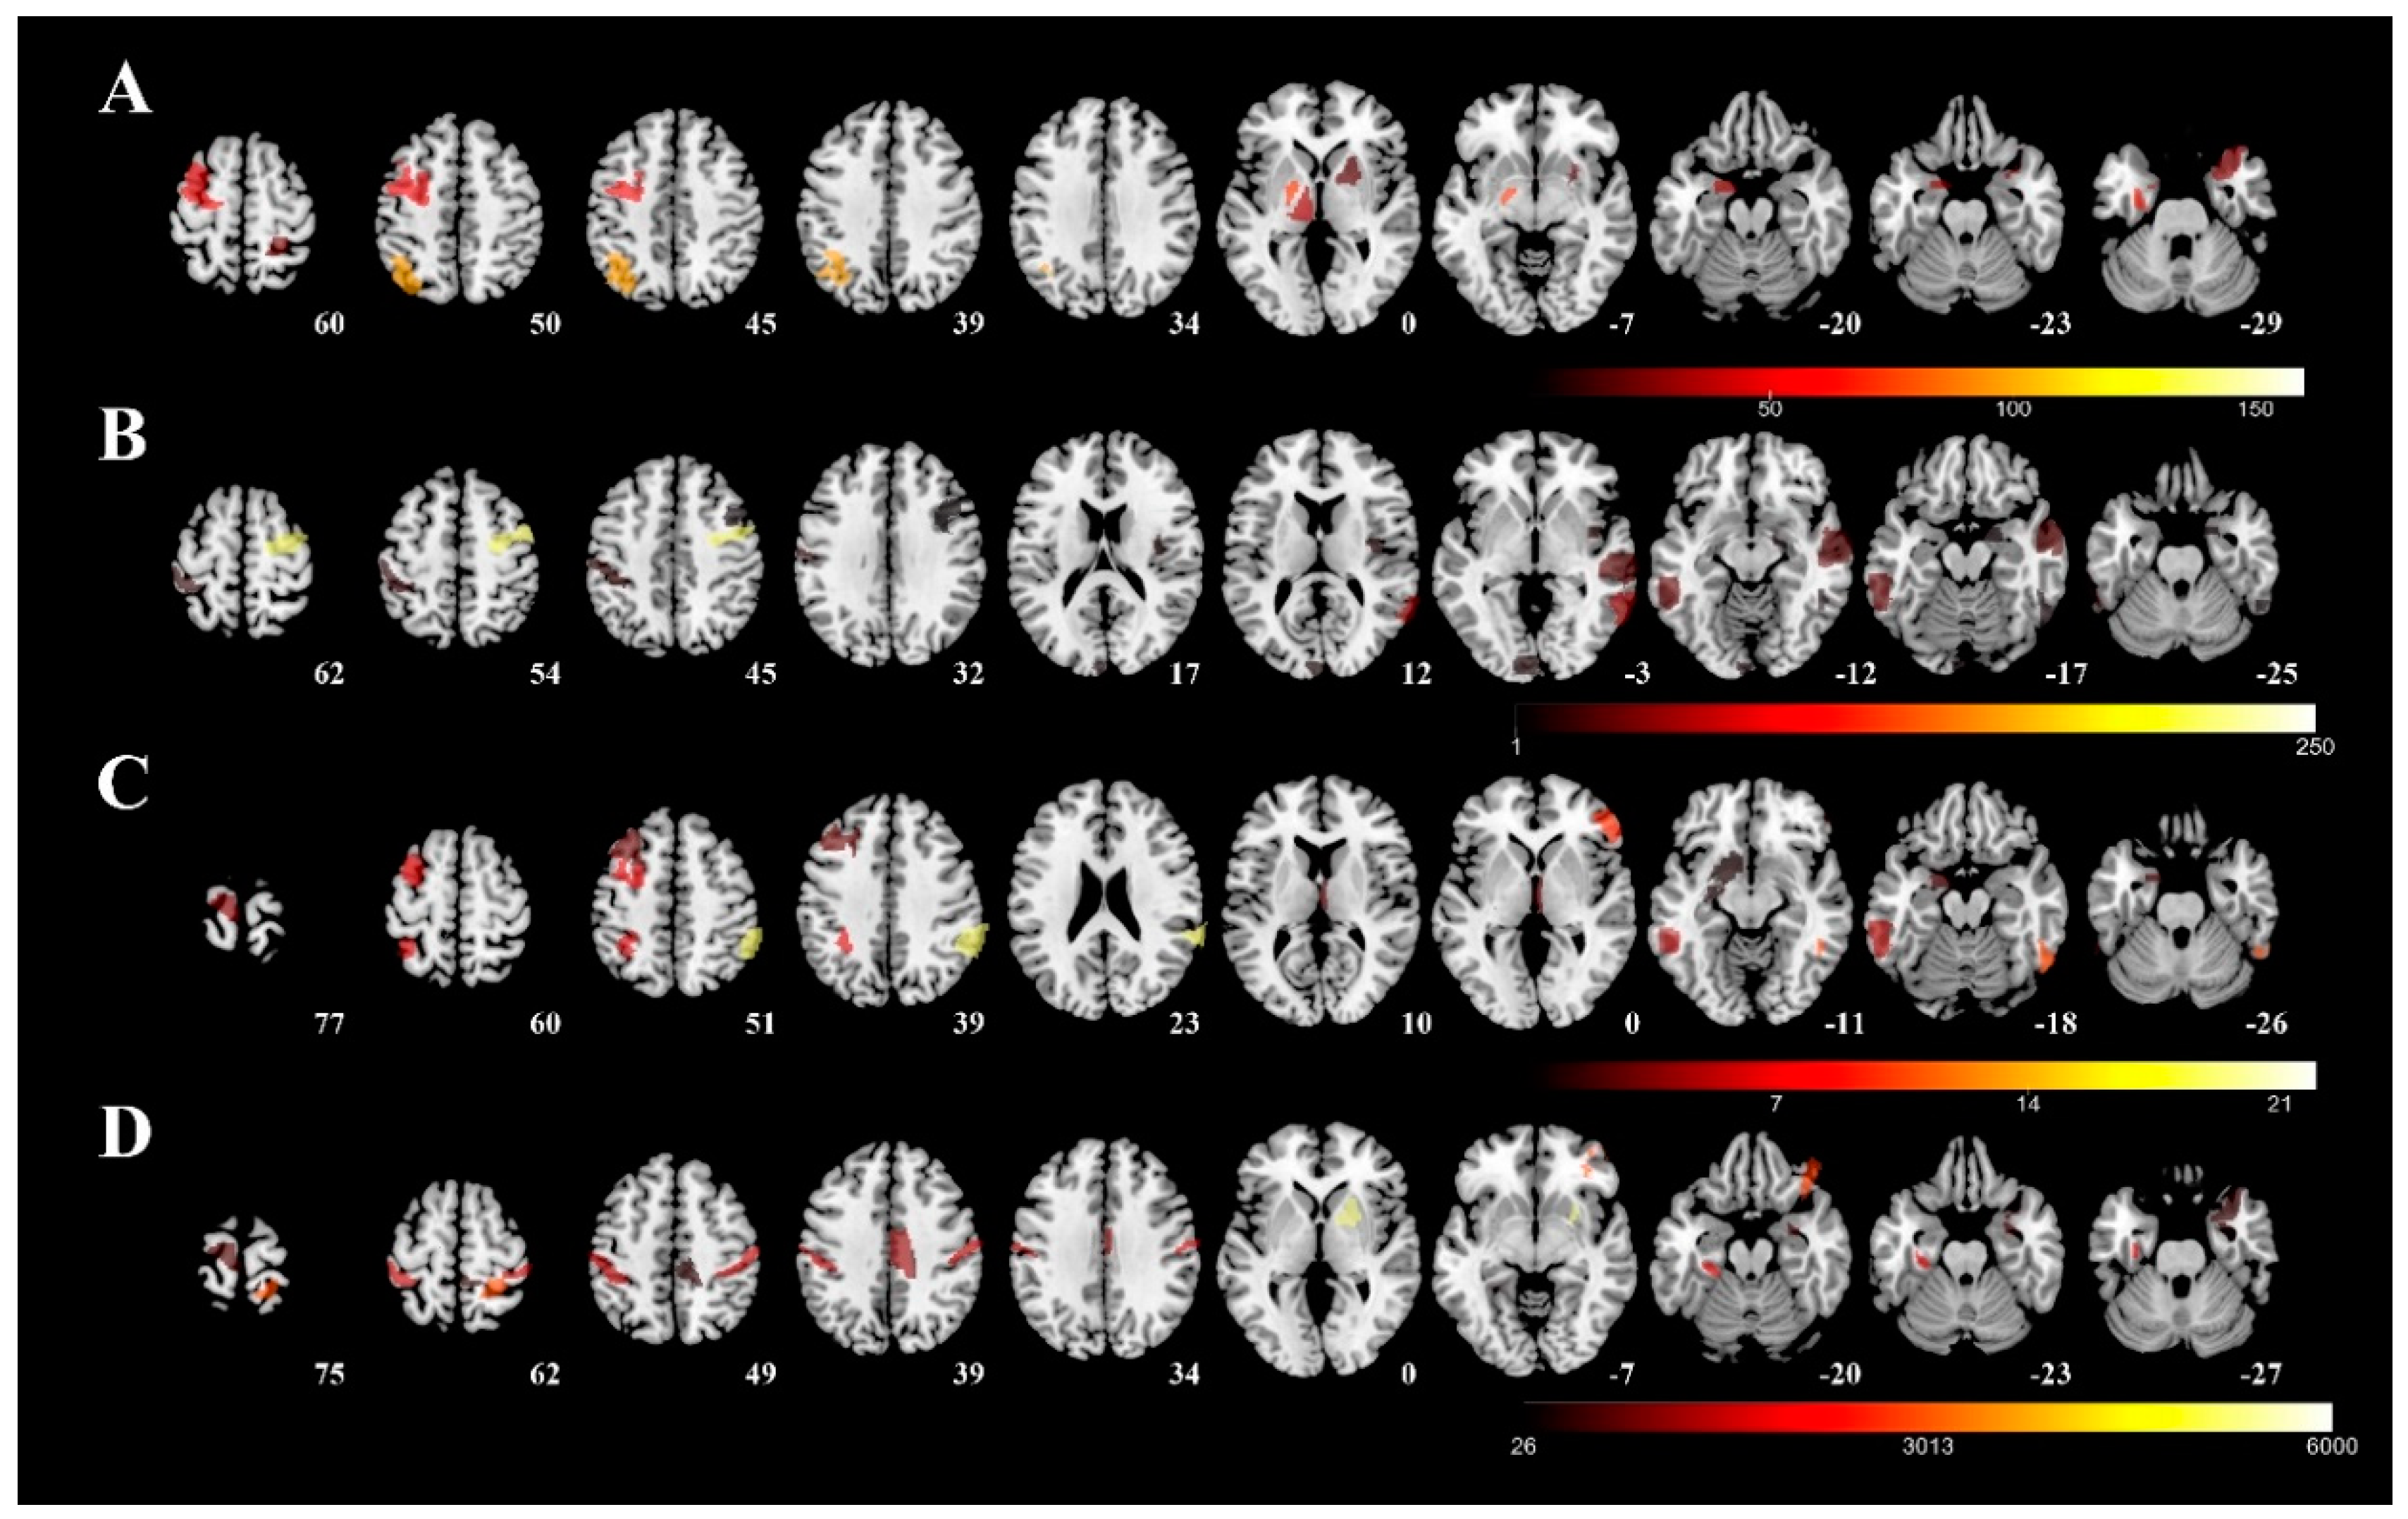

3. Results